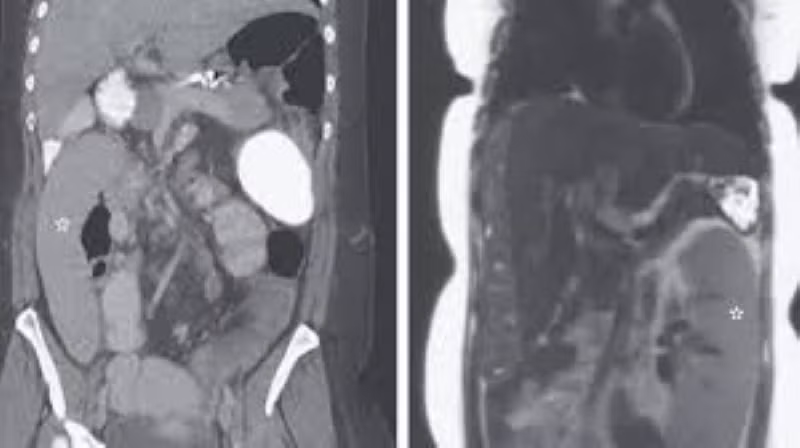

Tại khoa cấp cứu, các bác sĩ đã tiến hành lần chụp cắt lớp mới và phát hiện chỉ trong khoảng thời gian ngắn đó, lá lách của cô đã di chuyển hoàn toàn sang phần đối diện trên cơ thể.

Trong trường này, khi một người phụ nữ 36 tuổi đến khám tại Michigan Medicine ở Ann Arbor, các bác sĩ đã tìm thấy lá lách của cô ở bên phải của bụng. “Nó đã di chuyển khoảng 30cm” - TS Alexander Wester, bác sĩ nội trú về nội khoa tại Michigan Medicine trao đổi với Live Science.